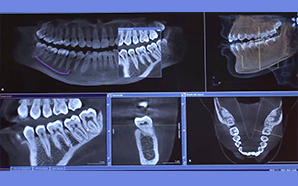

Somos una empresa siempre a la vanguardia, El Laboratorio de Radiología Diagnóstica en Ortodoncia, S.A. de C.V. tiene para todos los cirujanos que deseen contar con tecnología de punta el servicio de Radiología Digital más avanzado de México y el Mundo, que ya no requiere de escaneo, proceso selectivo, revelado, ni productos químicos, además ofrece mínimos niveles de radiación.

CALIDAD SIEMENS, CALIDAD ALEMANA, CALIDAD SIRONA